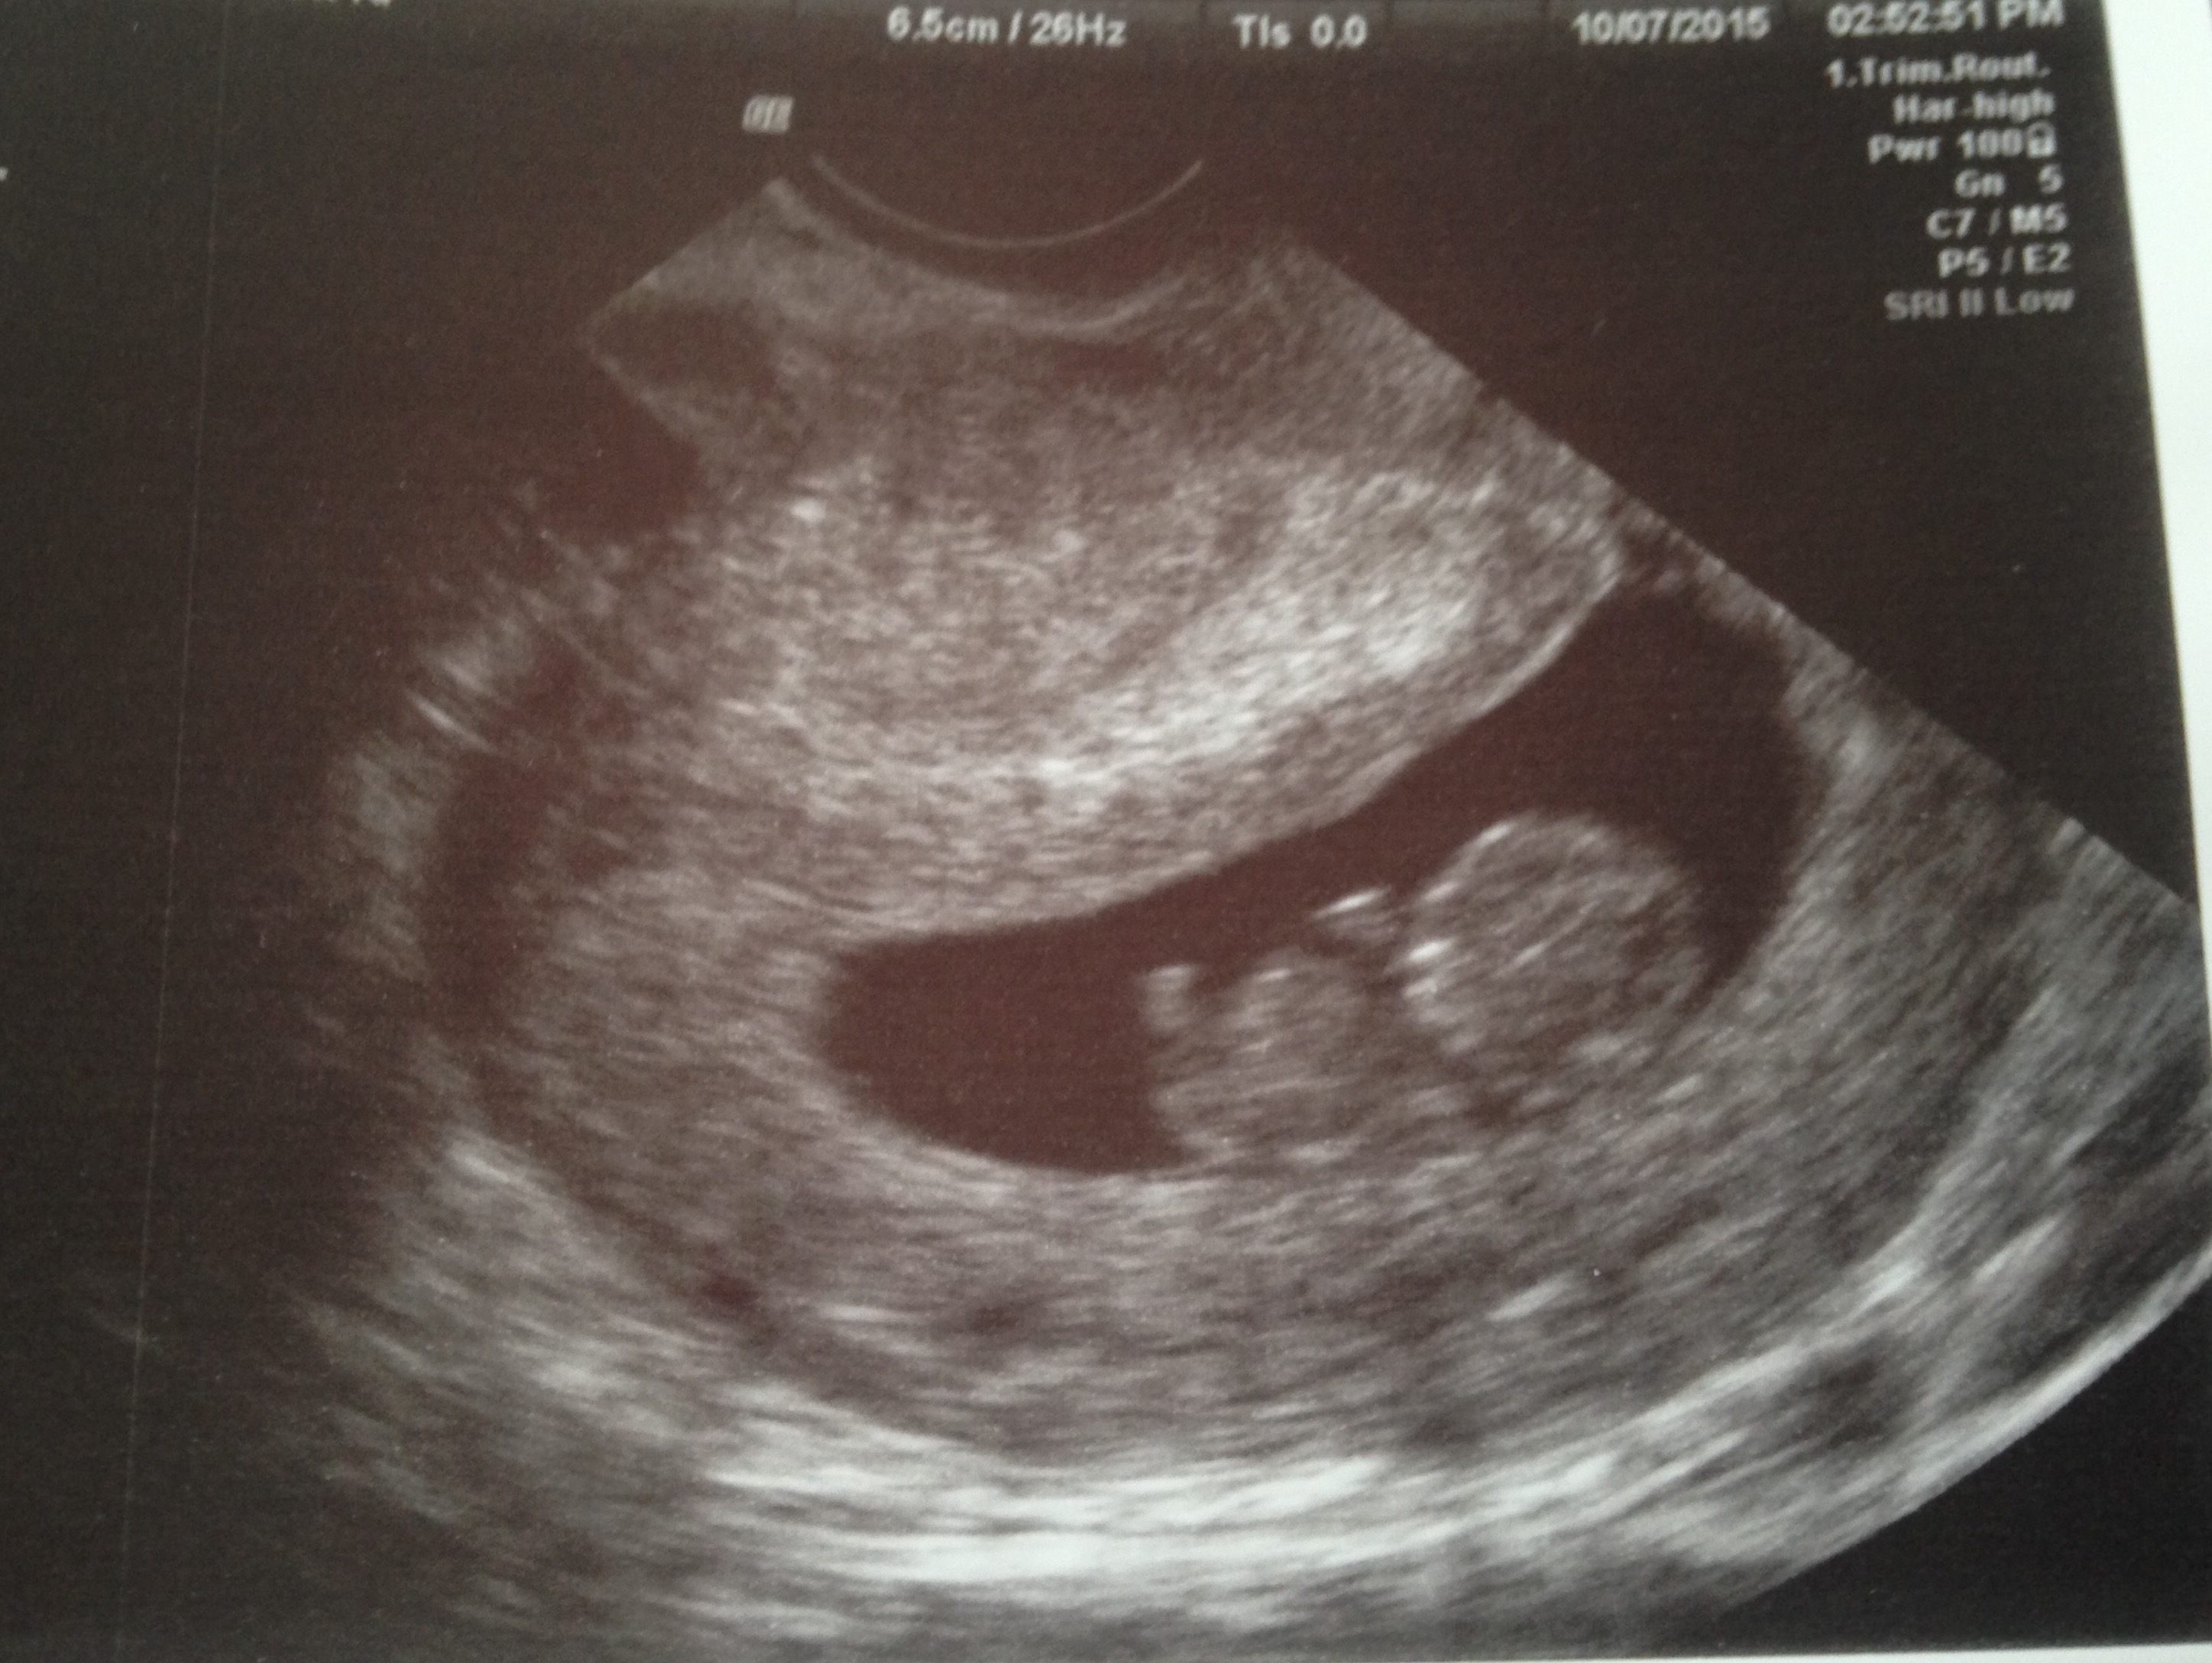

This baby looks chill to me, kicking back with their feet up

Im 8wks today and went for my first ever ultrasound after 2 mc. It was great. I was measuring around 9wks though, which is also a plus! We got to hear the strong heart beat and see it wiggle around! It is just so amazingwhat our bodies do!